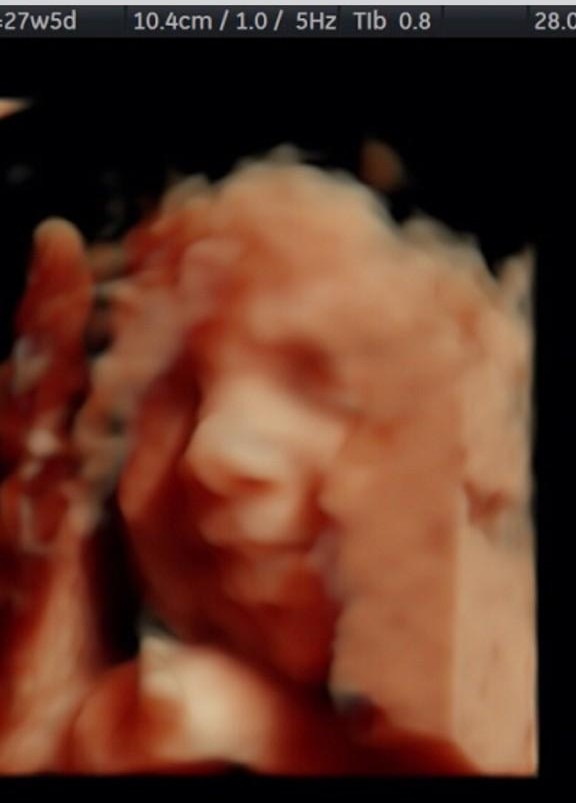

Su nacimiento tiene historia. De entrada, su segundo nombre representa la constancia que sus padres Marcos González Coghlan y Eliza Alcocer Pulido debieron de tener para poder concebir un hijo. Y es que después de dos abortos naturales y seis años de tratamientos el 6 de julio de 1982, por fin, pudieron ver por primera vez los ojos de su primogénito, a quien decidieron llamar igual que su padre.